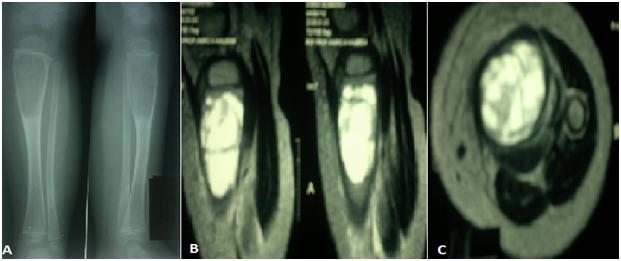

Follow up ranged from 18 months to 4 years for all patients. Close follow up until clinical improvement and radiological consolidation of the cyst. Pain Score according to Healing time ranged from 21 - 90 days with average 42.2 days. Motion of the arm as patients can move their arm without pain was allowed. Weight bearing for the lower limbs also had been allowed as patients felt pain subsided even there is no complete healing radiological. Painless non supported gait was observed and normal full activity with returning to their ordinary activities for all patients. Sports activities like football and running were return to normal in 7 children five out of them had tibial cyst (Figures 2 & 3) and other two patients had proximal femoral cyst (Figures 4 & 5) were returning to their normal sport activities. VAS ranged from 3-9 with average 5.7 which was improved to average 1.5 at final follow up (Figure 6). At final radiological evaluation we found all cases had consolidated felling of cysts by bony tissue in X-ray film and continuity of the cortical osseous structures. No cases of recurrence were observed for the last follow up of all patients.

In this study we have 5 cases (31.25 %) (2 cases of proximal tibial cyst and 3 cases with proximal femoral cyst) had juxtaarticular aneurysmal huge cyst and no needs for adjuvant material during intralesional injection of BMA with complete consolidation. Special consideration is necessary in dealing with ABCs that are near open physes. In literature there is a special consideration then operating around physes. The reported rate of physeal injury is significant, and patients and their families must be made aware of this possibility. Furthermore, it has been shown that attempts to spare the adjacent physes by performing less ¬than aggressive curettage of ABCs have resulted in increased risk of local recurrence in patients with open growth plates.15,16